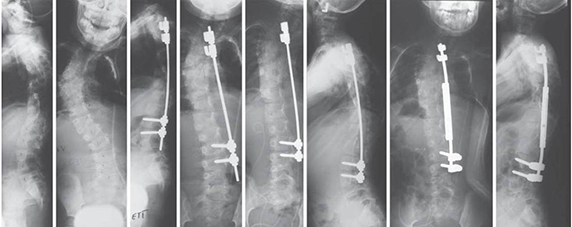

A veleszületett gerincferdülés tekintetében

Congenitalis scoliosis (veleszületett gerincferdülés) esetén a gyermekeket általában konzervatív úton (fűző, gyógytorna, egyéb fejlesztés) nem kezelik, ezek nem szükségesek (nem hatásosak). Dévény-torna, más terápia nem szükséges, hiszen ezek a csontos struktúrát nem befolyásolják. Alapvetően mindig a gerincsebész szakember egyénileg dönt a kezelésről. Érdemi kezelés (megfigyelés) a gyermek stabil állása után, egyéves kor körül kezdhető.

A kezelés menete, kezelési módok